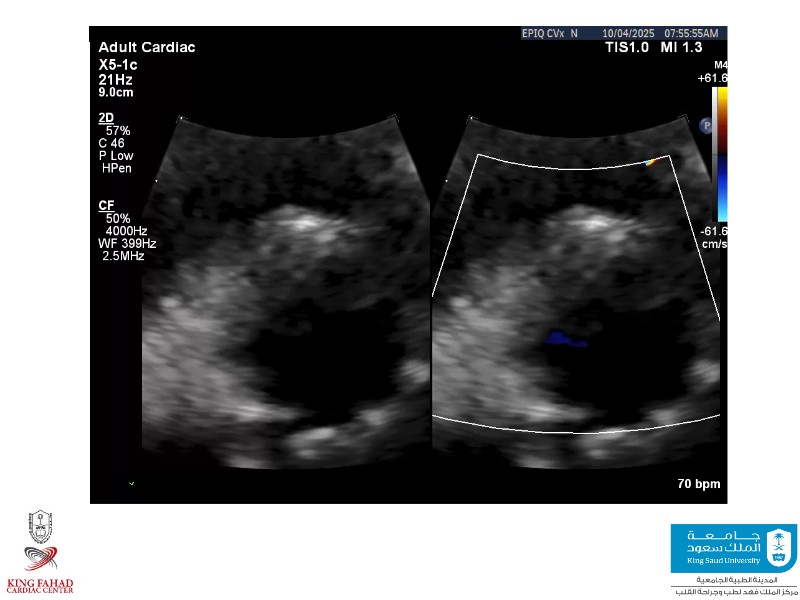

Second valve strategies with SAPIEN 3 Ultra RESILIA

This session helps you anticipate and address complex scenarios such as mitral valve-in-valve, TAV-in-SAV, and valve-in-valve-in-valve procedures. Learn from expert case discussions that explore procedural strategies, technical challenges, and best practices to optimize outcomes in redo structural heart interventions.